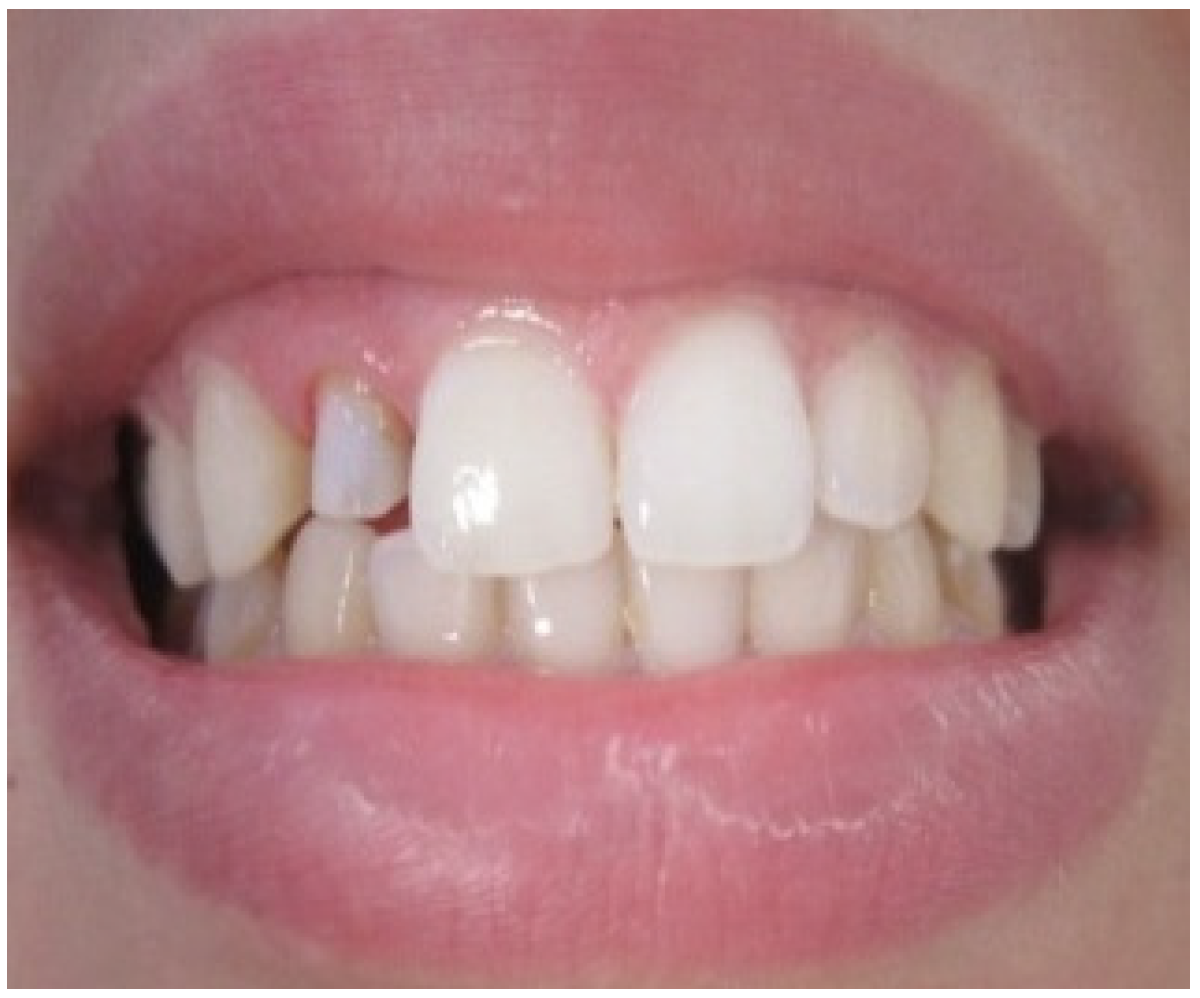

A 25-year-old dental student presented to the department of prosthetic dentistry with a chief complaint of poor aesthetics due to her imperfect metal ceramic single crown in the lateral incisor. She was bothered about the visible dark areas under the crown margins and requested an aesthetic rehabilitation. She also expressed her dissatisfaction with its color and shape. Intra oral examination showed dark gingival margins in the lateral incisor caused by metal frame (Figure 1). Soft tissues were evaluated as healthy with a wide band of attached gingiva in the maxillary region and a good oral hygiene.Visual assessment and Periodontal probing revealed a thick healthy gingival biotype with gingival thickness of 2 mm. and a sulcus depth of 2 mm. Bone sounding revealed a crest position in close relationship relative to anticipated post-surgical gingival margin level (2.5 mm). As the patient presents a thick periodontal biotype, this would significantly influence the post-operative procedure in favor of the esthetically desired outcome as this type is less prone to post-surgical recession.

Figure 1. Intra oral view showing the grayish shadow caused by the metal based crown.